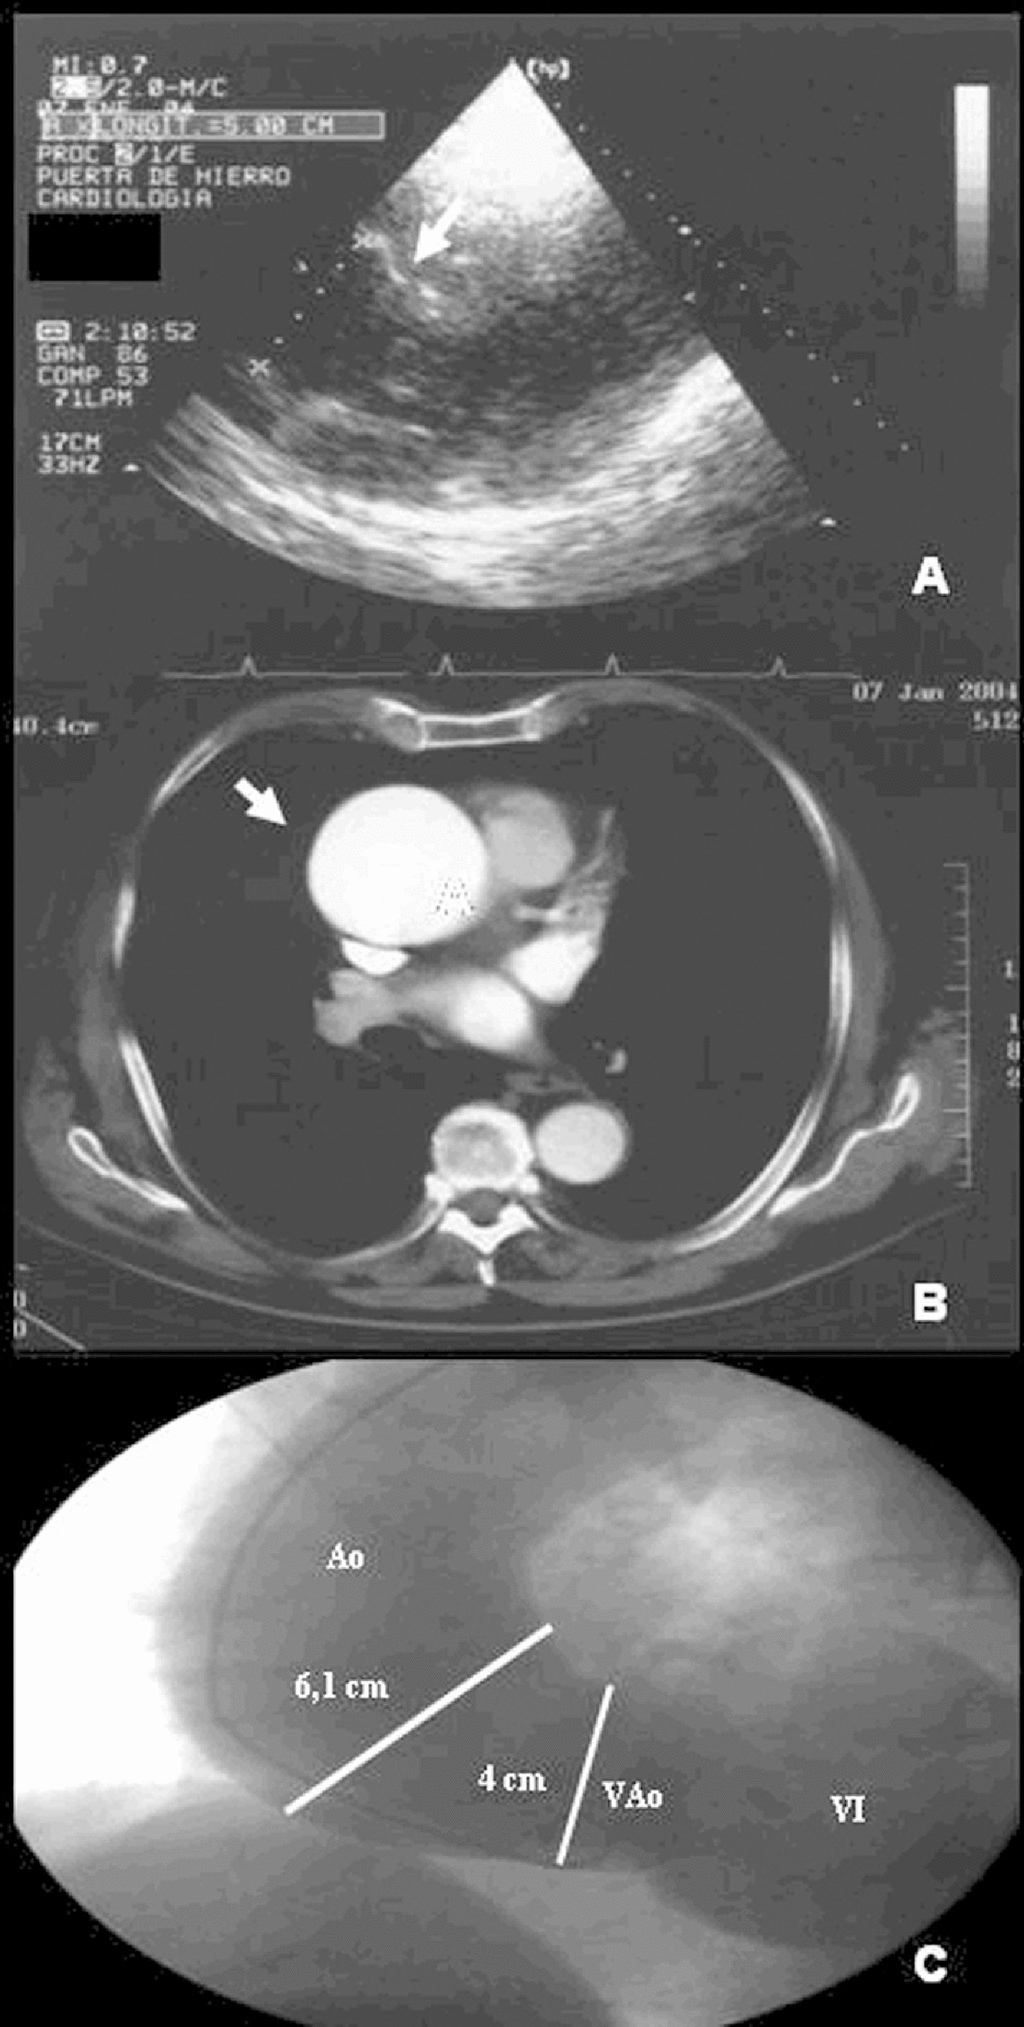

Se realizaron diferentes pruebas complementarias. La ecografía-Doppler descartó trombosis venosa o quiste de Baker. El electrocardiograma mostró un bloqueo anterior de la rama izquierda y fibrilación auricular. La radiografía de tórax puso de manifiesto un ensanchamiento de la silueta de la aorta torácica. El ecocardiograma evidenció una insuficiencia aórtica grave y una dilatación de la aorta ascendente, con un diámetro de 50 mm (fig. 1A). La tomografía computarizada (fig. 1B) confirmó la presencia de un gran aneurisma de la aorta ascendente, sin signos de disección. El estudio hemodinámico previo a la cirugía puso de manifiesto una dilatación aneurismática de la aorta ascendente (fig. 1C).

Figura 1. A) Ecocardiografía que pone de manifiesto un aneurisma de aorta ascendente. B) Tomografía computarizada que muestra la existencia de aneurisma de aorta ascendente. C) Aortografía realizada en proyección oblicua anterior izquierda que muestra dilatación aneurismática de aorta (Ao) ascendente. Contrastación de ventrículo izquierdo (VI) similar a la Ao, que indica la presencia de insuficiencia aórtica grave. VAo: válvula aórtica.